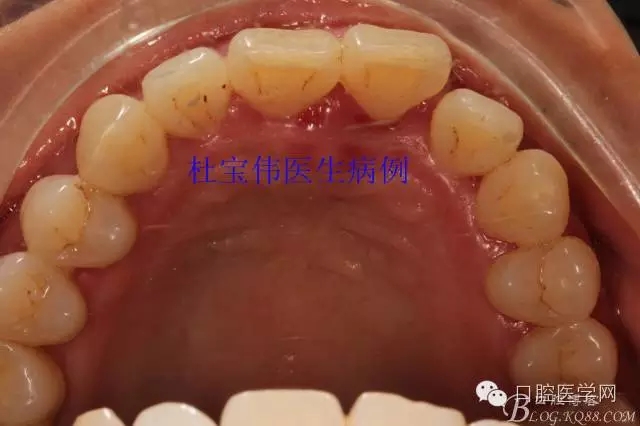

病例二術(shù)前照片